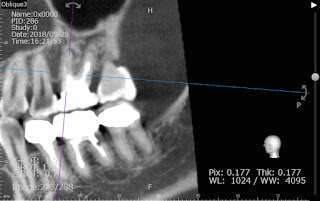

根管の形態を把握するためにCTを撮影して見ます。

そのまま未処置根管が見つかることもありますが、大抵根管が見つからないといった原因からの再治療では石灰化していて見えないことの方が多いです。

それでも歯根の形態から根管の有無を推測できるので、治療を開始しました。

器具が入っている箇所が、見つからなかった根管になります。

上顎の大臼歯で治療が難しく、再治療になる原因となる箇所です。